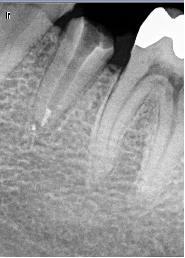

cette couronne est totalement inadaptée au niveau cervicale d'après ta radio

je pense que t'as du bol d'avoir pu descellé sans fracturer la racine étant donné la taille du tenon

D'un autre coté, vu la taille du pivot, c'est un miracle s'il n'y a pas fracture.

Moi ce que çà m'évoque c'est une possible perforation de la racine par le tenon dans le sens vestibulo-lingual. Vu la longueur du tenon c'est possible. Le tenon a-t-il un axe bizarre ? Un saignement dans le canal c'est pas bon signe.

desceller un pivot pareil ! et à coté de çà radiologiquement parlant y avait pas forcement obligation d'intervenir.

Si c'est parti tout seul, c'est fellé/fracturé quelquepart.

Souvent impossible à voir avec RX.